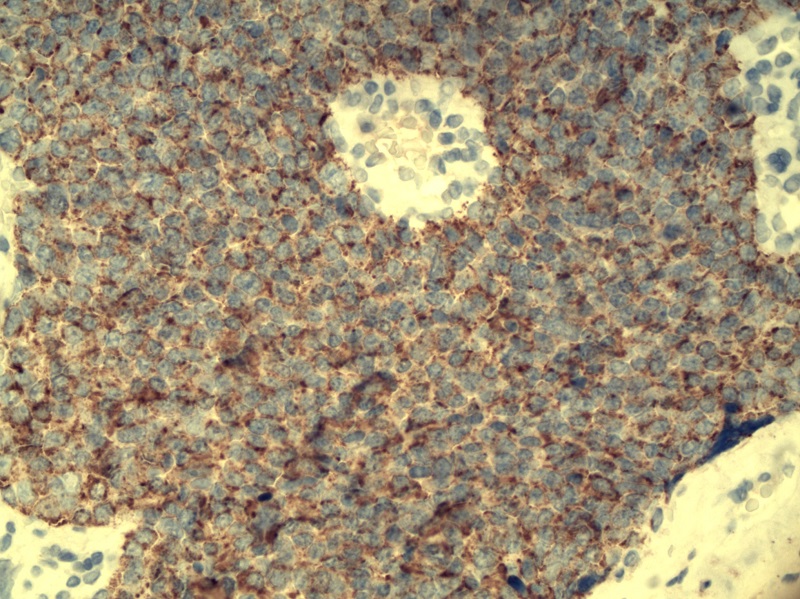

Cechy cytologiczne: Gruczoły szyjki macicy wyścielone są przez nieprawidłowe, kolumnowatego kształtu komórki gruczołowe (Fot. 1). Pod względem cytologicznym przypominają one raka gruczołowego inwazyjnego. Ich jądra komórkowe są hiperchromatyczne, wydłużone, cygarowatego kształtu i posiadają grube ziarnistości chromatyny. Stosunek jądrowo-cytoplazmatyczny przesunięty jest na rzecz jądra. W cytoplazmie występują złogi śluzu wewnątrzkomórkowego (Fot. 2). Patologiczne figury podziałów mitotycznych… Dowiedz się więcej: Gruczolakorak in situ szyjki macicy (łac.: adenocarcinoma in situ [AIS] colli uteri) - Pracownia Genetyki i Biologii Molekularnej